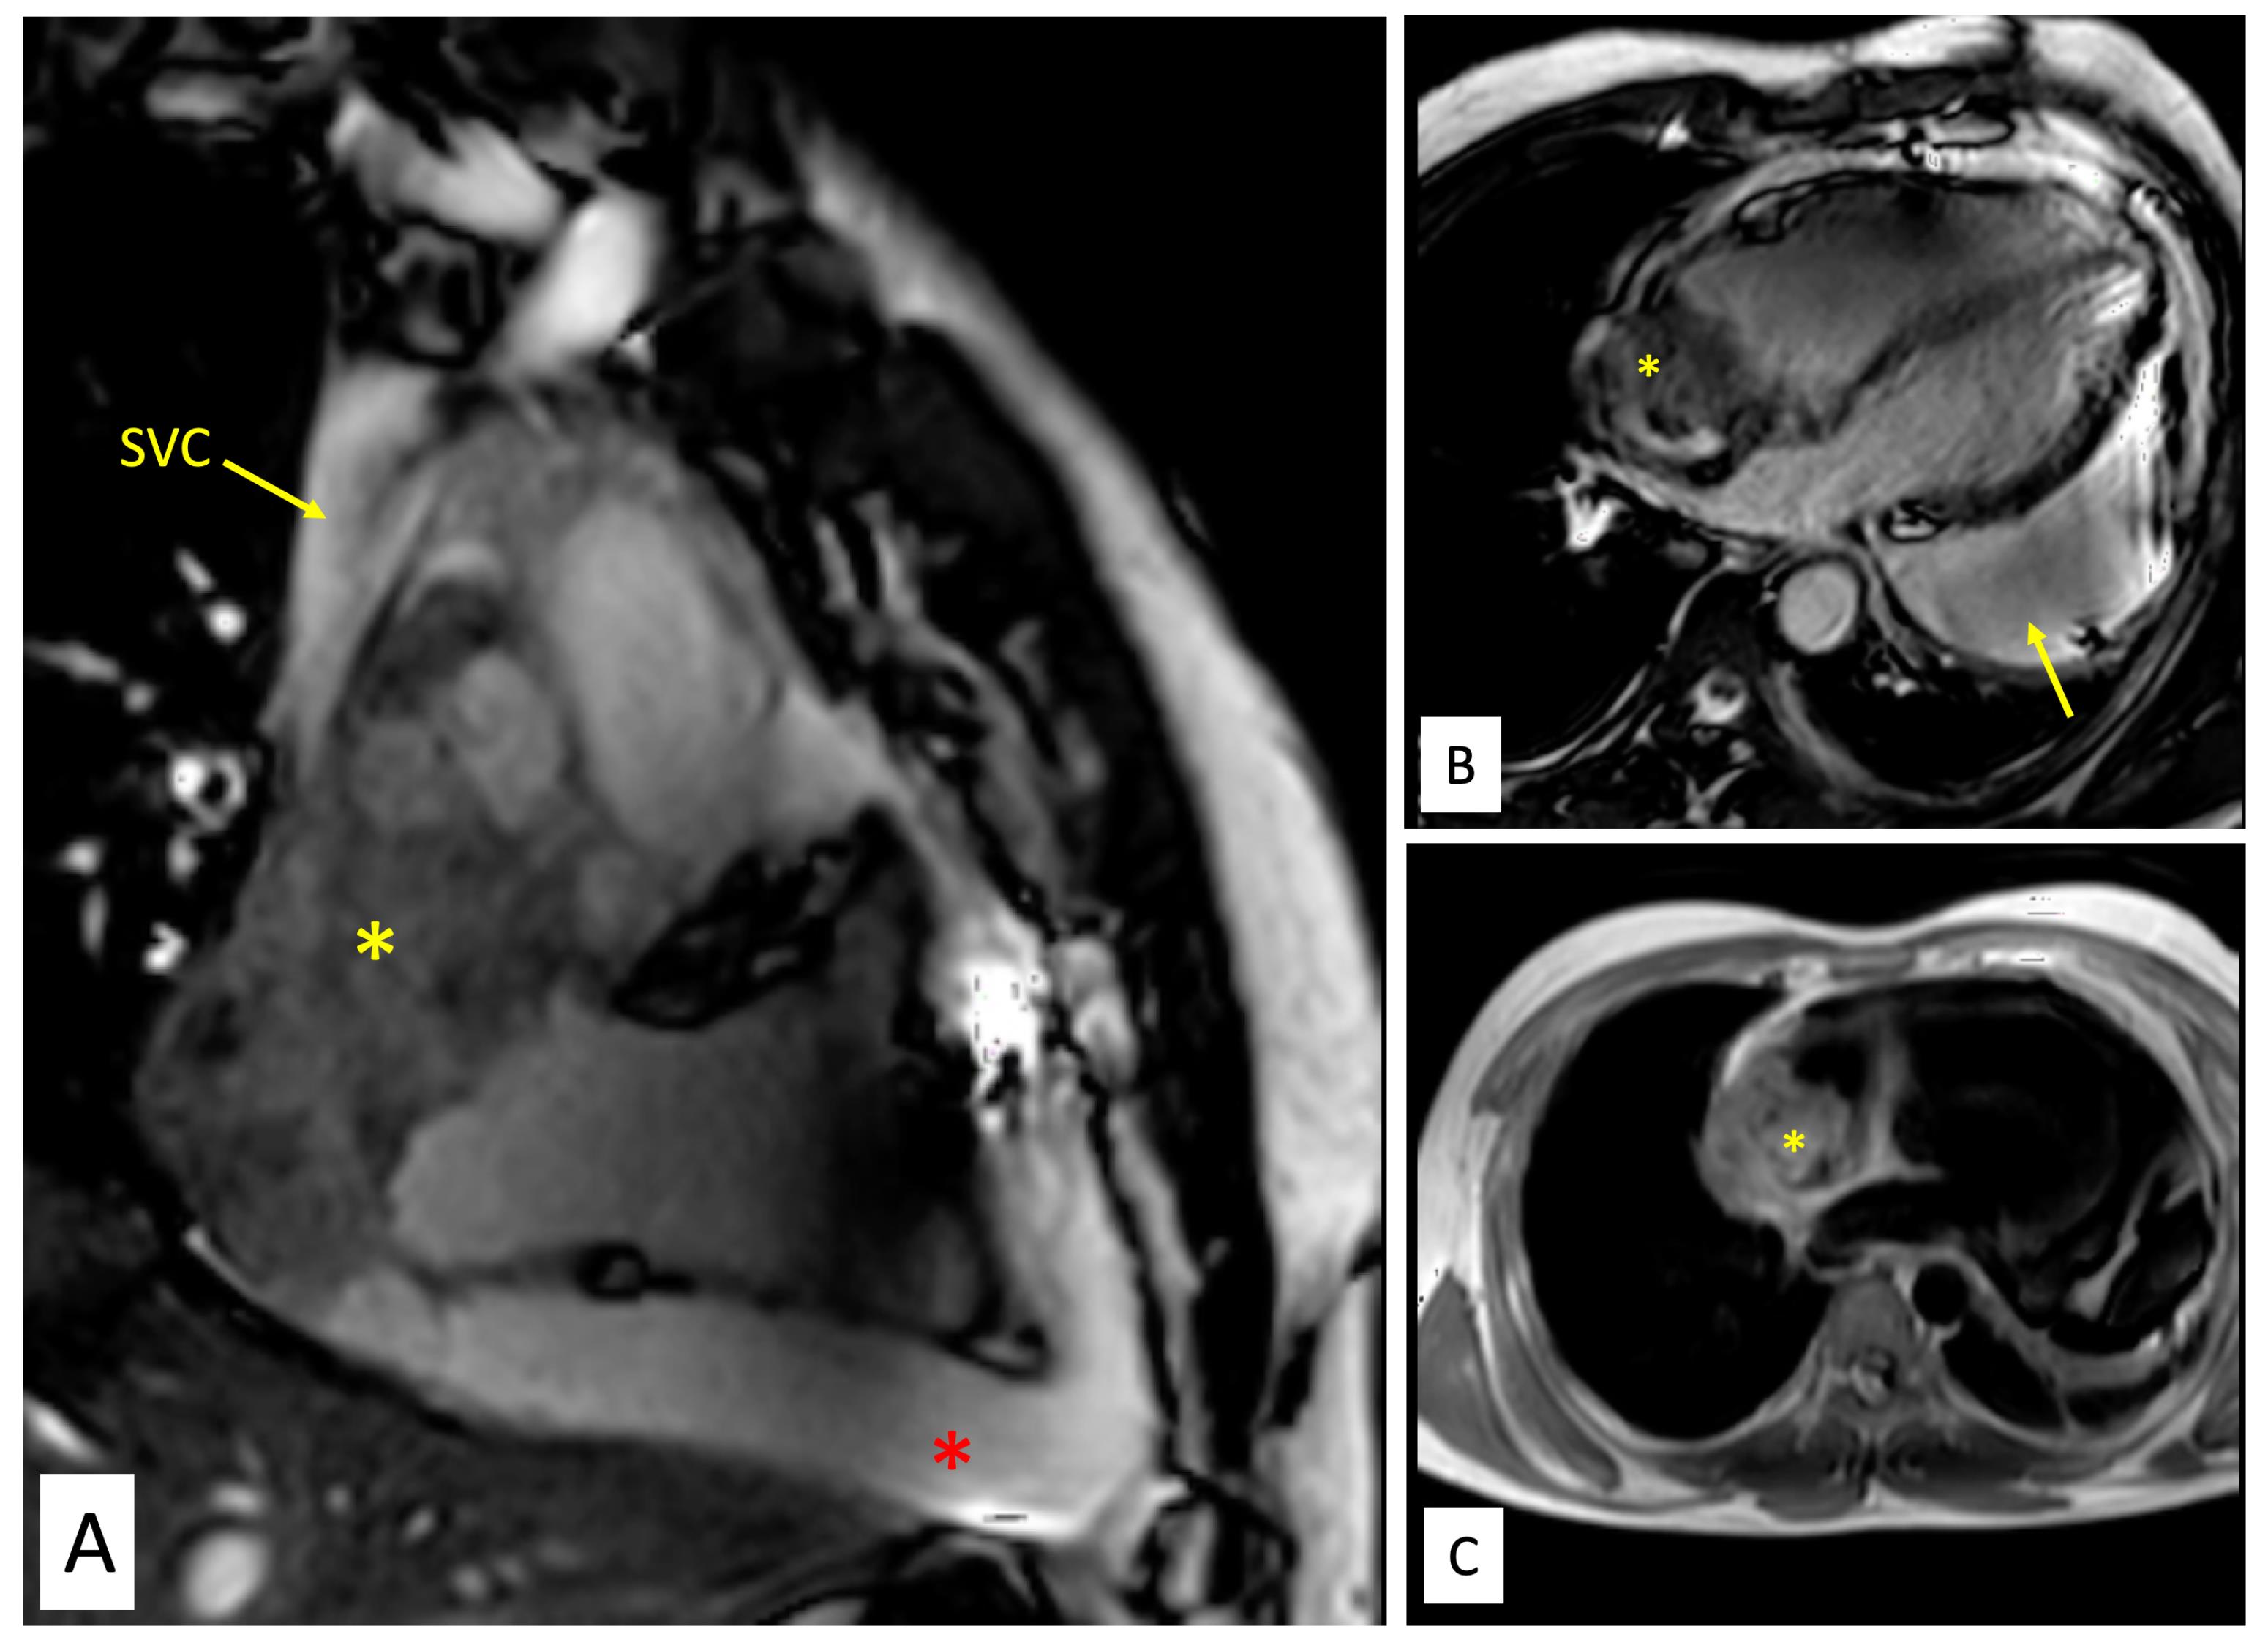

Figure 1.

Echocardiography, CT and PET findings. A. Echocardiographic subcostal four chamber view demonstrating large multilobulated mass in the right atrium (yellow asterisk) with pericardial effusion. B. Echocardiographic parasternal long axis view showing large pericardial effusion (yellow asterisk). C. Echocardiographic parasternal short axis view showing large multilobulated mass in the right atrium close to the superior vena cava (yellow asterisk). D. Echocardiographic subcostal bi-caval view showing lobulated mass in the right atrium (yellow asterisk). E. A contrast enhanced computed tomographic image shows an irregular, broad-based, ‘cauliflower like’ mass abutting the lateral wall of the right atrium, with local infiltration into pericardium and a moderate pericardial effusion. F. Corresponding positron emission tomography (PET) image depicts high fluorodeoxyglucose (FGD) uptake by the right atrial mass, suggesting a metabolically active tumor, likely malignancy.

Contrast enhanced cardiac computed tomography (CT) showed an irregular, broad-based, ‘cauliflower like’ mass abutting the lateral wall of RA with a heterogeneous streaky (sun ray) post-contrast enhancement (Figure 1E). There was local pericardial infiltration with associated moderate pericardial effusion. An aggressive mass in RA, metastasis or angiosarcoma, was suspected. There was no evidence of any primary tumor anywhere in chest or abdomen on CT scan. Cardiac magnetic resonance (CMR) imaging showed a T2-hyperintense mass measuring 64 mm x 44mm involving anterolateral wall of RA, with thickening of adjacent pericardium, superiorly invading cavo-atrial junction and extending into the superior venacava (SVC) (Figure 2A-2C). Invasion of SVC favours angiosarcoma over lymphoma; lymphoma usually presents as an insinuating mass without displacement or compression of vascular structures. The rapidly growing mass in the CMR compared to the CT image 1 week earlier, infiltration into pericardium and SVC pointed towards a rapidly growing malignant tumor. ATT was discontinued as there was a lack of improvement in symptoms and imaging evidence of likely malignancy. Positron emission tomography (PET) scan revealed an FDG-avid mass in the RA wall with extension into mediastinal structures and similar uptake in right lower paratracheal, prevascular, paraortic & paracardiac regions (Figure 1F). The mass was seen to infiltrate ascending aorta, pulmonary artery and SVC. It showed areas of photopenia & hypodensity within mass, suggestive of necrosis. No metastasis to distant organs was noted. Patient had further deterioration of dyspnea and in search of a definitive diagnosis, an endomyocardial biopsy was planned after discussion with heart team. The tissue analysis, however, did not yield any malignant cells. After discussion with the family, open biopsy using a lateral thoracotomy approach was performed. A few hours after the procedure, patient had sudden and rapidly progressive shock and worsening of respiratory distress requiring mechanical ventilation. Echocardiogram revealed large pericardial effusion with tamponade, which on aspiration yielded hemorrhagic fluid. With a possibility of active bleed from the vascular tumor or a vessel, a midline thoracotomy was done to localize and stop bleeding. The patient’s hemodynamics worsened during the procedure and he succumbed. Histological examination of the biopsied tissue revealed large areas of hemorrhage with fibrin & necrosis. Preserved areas showed a tumour arranged in sheets and short intersecting fascicles. There were slit like spaces with red blood cells. Tumor cells were moderately pleomorphic, had round-to-oval nuclei with vesicular chromatin, conspicuous nucleoli and moderate amount of cytoplasm. These cells were positive for CD31(membranous) and negative for desmin and PanCK(pancytokeratins) which was suggestive of angiosarcoma.